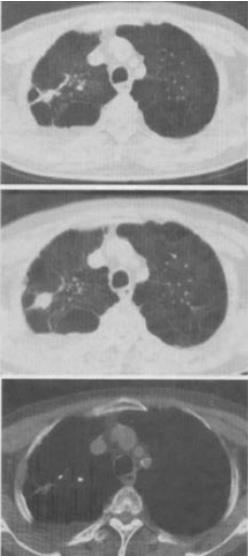

患者男,76岁,气喘数年,胸痛1个月余,结合图像,最可能的诊断是()。

A:右上肺结核球

B:肺间质纤维化

C:右上肺瘢痕癌

D:右上肺错构瘤

E:右上肺肉瘤